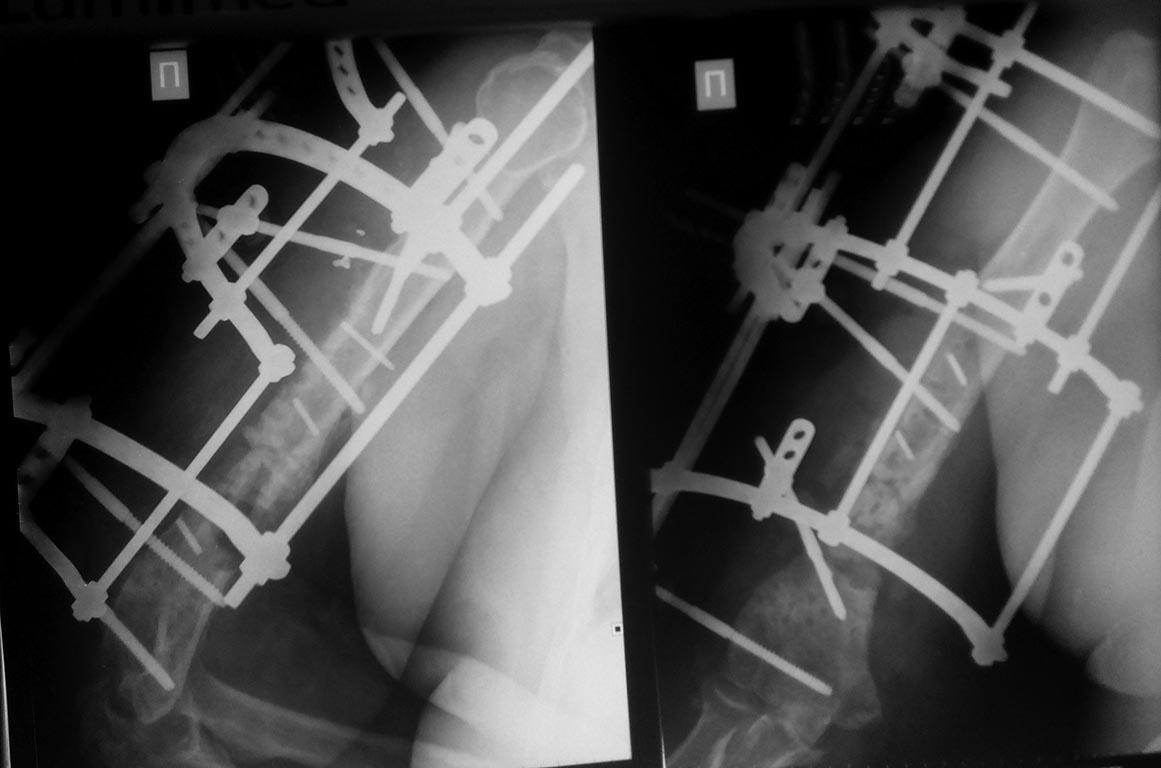

после неудачного реостеосинтеза